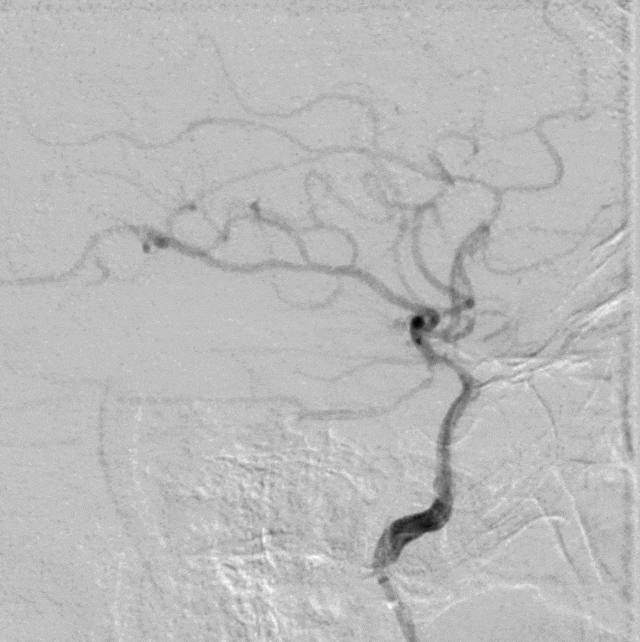

15min后,观察正侧位、3D旋转,可见狭窄较前明显改善。

什么叫桡鞘【例久弥新】寻道于桡——瑞康通5.5F Introsky X导管鞘经桡取栓一例_https://www.jmylbn.com_新闻资讯_第25张

什么叫桡鞘【例久弥新】寻道于桡——瑞康通5.5F Introsky X导管鞘经桡取栓一例_https://www.jmylbn.com_新闻资讯_第26张

什么叫桡鞘【例久弥新】寻道于桡——瑞康通5.5F Introsky X导管鞘经桡取栓一例_https://www.jmylbn.com_新闻资讯_第27张